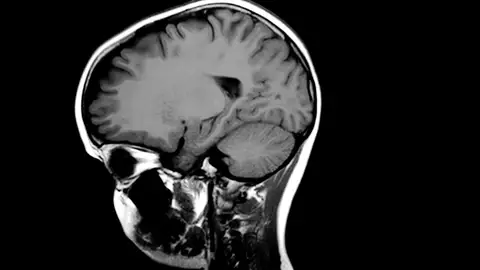

Según la Universidad de Barcelona, en un estudio que elaboraron en 2020, la encefalitis anti-NMDAR es una enfermedad cerebral autoinmunitaria que se confunde frecuentemente con un trastorno psiquiátrico porque provoca psicosis y otras alteraciones del comportamiento.

La encefalitis anti-NMDAR es una enfermedad autoinmune que causa inflamación en el cerebro. Este proceso se desencadena cuando el sistema inmunológico ataca accidentalmente los receptores NMDA en las neuronas cerebrales. Estos receptores son importantes para la comunicación entre las neuronas.